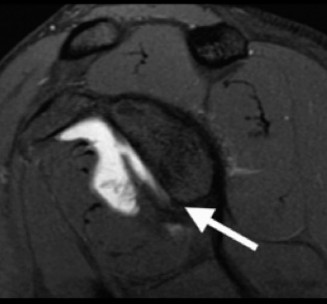

Advanced imaging is mandatory when bone loss is suspected. While Magnetic Resonance Imaging or MR Arthrogram is excellent for evaluating the capsulolabral complex, rotator cuff, and cartilage, three dimensional Computed Tomography is the gold standard for quantifying osseous defects.

The en face view of the glenoid on 3D CT with the humeral head digitally subtracted allows for precise measurement. The "best fit circle" method is commonly utilized. A circle is drawn matching the contour of the inferior and posterior glenoid, and the area or width of the missing anterior bone is calculated relative to the area or diameter of the circle. The Pico method compares the surface area of the injured glenoid to the contralateral normal glenoid, assuming the contralateral shoulder is uninjured. The humeral head must also be evaluated to calculate the glenoid track, measuring the width of the Hill-Sachs lesion and the intact anterior glenoid bone bridge.